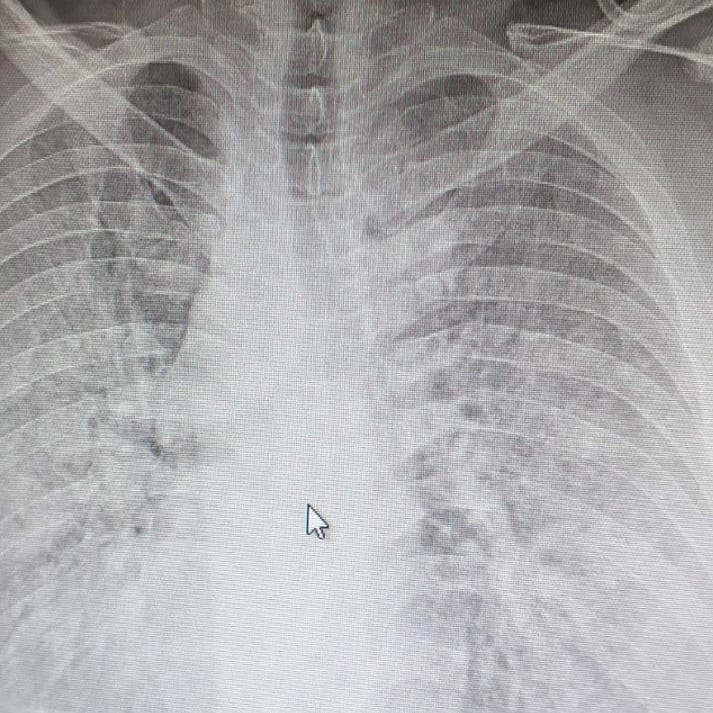

Besim Bytyçi, i cili është internist dhe reumatolog, ka shpërndarë një rëntgen të mushkërive të një 30-vjeçari i cili është i infektuar me koronavirus.

Ai tha se 30-vjeçari i infektuar me koronavirus që është i shtrirë në spitalin e Ferizajt, nuk ka sëmundje të tjera shoqëruese, por virusi ia ka katandisur mushkëritë.

“Shumica e njerëzve po e kalojnë këtë sëmundje më pak simptoma. Por një pjesë e tyre po luftojnë mes jetës e vdekjes. Unë nuk po dua të bëj panik, por po ju flas nga përvoja e përditshme që jam duke punuar në spitalin e COVID- it në Ferizaj. Kjo sëmundje nuk pyet moshë. Aty kemi të hospitalizuar njerëz të kategorive të ndryshme, pleq djem e vajza edhe të reja, në mesin e tyre edhe mjekë dhe infermierë. Shikoni një rentgen të mushkërive si është katandisur nga ky virus. Ky rentgen nuk është i një plaku 90 vjeçar, por i një të riu nën moshën 30 vjeçar që më herët nuk ka pasur kurrfarë sëmundje shoqëruese”, ka shkruar Bytyçi në Facebook.